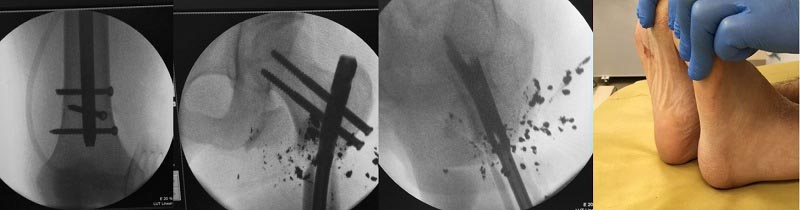

После первичной хирургической обработки и стабилизации перелома в АВФ

ведения раны на VAC в течении 7 дней отделяемое из раны вызывало

сомнение, проведена вторичная хирургическая обработка раны, удалены

костные отломки которые даже частично были лишены надкостницы, инородные

тела. С учетом поперечной линии излома торца проксимального отломка

торец дистального отломка частично резецирован (тоже был лишен

надкостницы). Повторный посев из раны , а/б терапия с учетом

чувствительности, VAC терапия продолжена. На фоне проводимой терапии -

рана активно гранулировала, контрольный посев из раны роста флоры не

обнаружил. Сегодня пациент оперирован - остеосинтез стержнем LAFN.

Репозицию выполнял в стержневом аппарате. Канал рассверлил. Рану ушил.

Контроль интраоперационный в приложении. Комментарии, критика

приветствуются.